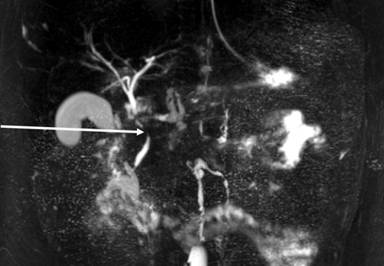

He came to the emergency room because he had felt abdominal pain in the epigastric area for two months, but the pain became constant and with increased intensity. He reported nausea and vomiting, but no modification of bowel habits. Clinical examination revealed stable hemodynamic signs but a marked tenderness with focalized guarding in the right hypochondrium and epigastric region. Laboratory analysis did not reveal anything specific, except elevated lipases at 696 U/L (reference range : 114-286 U/L). Abdominopelvic computed tomography (CT) (Figure 1) and then magnetic resonance imaging (MRI) showed kissing gastric ulcers of the antrum, with the posterior ulcus perforating the gastric wall into pancreatic parenchyma and a Balthazar C associated pancreatitis (Figures 2 and 3). Imaging also disclosed a left portal branch thrombosis and a portal biliopathy (with an amount of thin veins around the main biliary duct) (Figure 4). First, evolution was satisfactory with medical treatment (fasting, gastric protectors, and nasogastric tube). But pain returned with every attempt of food intake. Finally, an endoprosthesis in the pancreatic main duct was placed with a positive result and symptom resolution.

Figure 4. MRI showing main biliary duct narrowed by venous network called portal cavernoma (arrow). |

Furthermore, we discovered a thrombosis of the left branch of the portal vein and a portal cavernoma, also called portal biliopathy.

Portal cavernoma is an anarchic venous network in which hepatopetal portal blood circulates, caused by a chronic thrombotic occlusion of extra-hepatic portal system. At least 3 weeks are necessary for the cavernoma development [6, 7]. The causes of portal biliopathy are those of portal vein thrombosis: local causes such as malignant process, intra-abdominal inflammation, trauma, and iatrogenic, or general disorders such as thrombophilia (as frequent as 72% of cases) [6, 8].